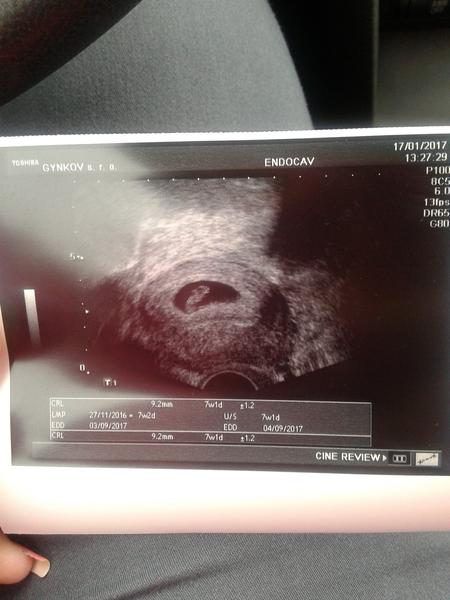

Na prvni fotce 5+2tt (vylouceno mimodelozni a byl videt zloutkovy vacek ) druha fotka 7+2tt uz krasne bilo srdicko 🙂 je pravda, ze zalezi na utz doktora, ale me v tech 5+2tt ani nenapadlo, ze by bylo srdicko, tak budte holky v klidu, do 8tt casu dost 😉

Toto je ma fotka 5+2

Vypada to jako prstynek a jdou videt 2 křizky ze neco měril..

Holky prosiiim.co myslite na ten ultrazvuk ze tam.je teda videt???

@petapal dekujii ale stejnej obrazek hako mam ja tam neni..zajimalo vy me co tam jako je viset na tom mem uzv.

Boze to je zase švahilština ta ma věta s překlepy...jen proste nikde sem nevidela obrazek jaky mam ja. .

@sukubka je to urcite v poradku, akorat to ma hodne priblizene 🙂

@sukubka je to v pořádku tři já našla na netu je to podobné